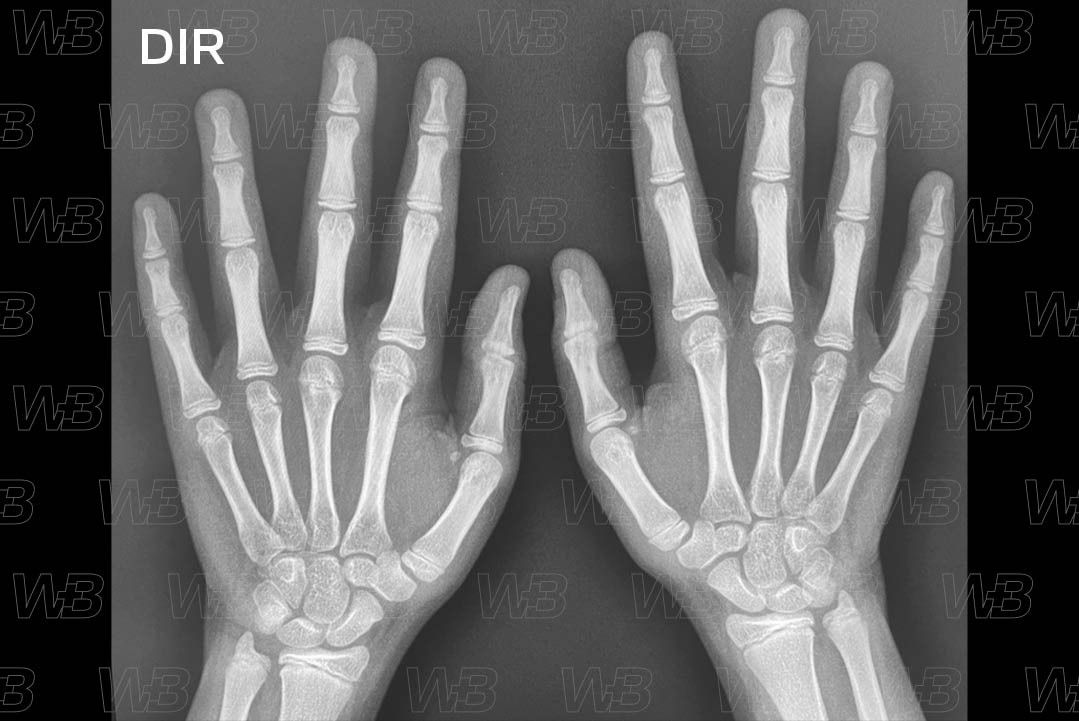

RADIOGRAFIA MÃOS E PUNHOS (IDADE ÓSSEA) [cms-watermark]

Feminino

13 anos:

• Fusão da epífise distal do polegar.